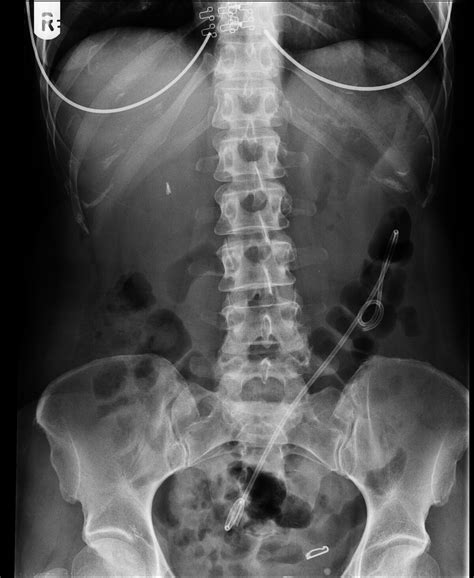

A bile duct stent is a synthetic tube—often made of plastic or metal—designed to be inserted into the bile duct to keep it open. The bile duct is a series of thin tubes that transport bile from the liver and gallbladder into the small intestine, where it aids in digestion. When this pathway becomes blocked, bile accumulates, leading to jaundice, severe pain, infection, or liver damage. The stent acts as a scaffold, ensuring that bile can flow freely into the digestive system once again.

These devices are primarily inserted via a procedure known as Endoscopic Retrograde Cholangiopancreatography (ERCP). During this minimally invasive procedure, a gastroenterologist uses an endoscope—a flexible, lighted tube with a camera—to navigate through the esophagus and stomach into the small intestine, reaching the opening of the bile duct to deploy the stent.

• Imaging: Using fluoroscopy (real-time X-ray), the doctor identifies the exact location of the blockage.

• Deployment: Once the location is identified, the stent is advanced through the endoscope and expanded within the narrowed area of the bile duct.